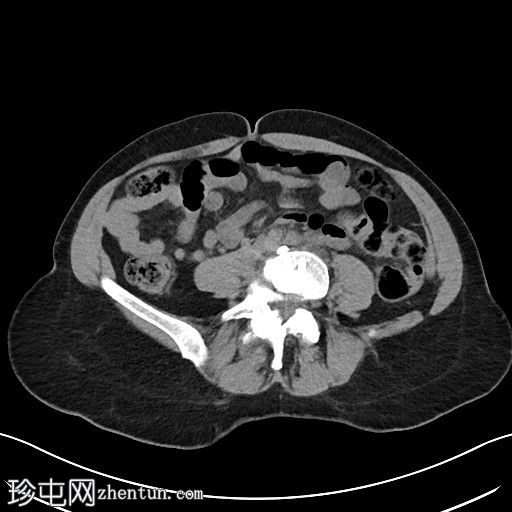

2.jpg

冠状位

平扫

左侧腹膜后可见一巨大囊性肿块,位于左侧腰大肌内侧,紧邻多个手术夹(ALIF手术所用),这些手术夹紧贴囊性肿块后壁。

膀胱已行引流管减压,并被囊性肿块向右侧推移。

子宫和左侧附件在囊性肿块前方保持正常的脂肪间隙,因此附件囊性病变的可能性较小。

左侧输尿管难以辨认,因为它位于囊性肿块下缘后方。

左侧腹膜后巨大囊性病变,符合术后淋巴囊肿。鉴别诊断包括血清肿、尿瘤和脑脊液积聚,但脑脊液积聚的可能性较小。